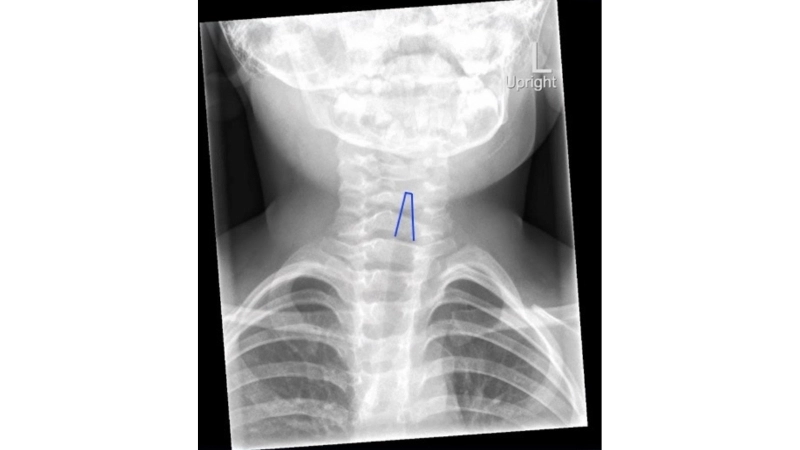

Image description of Croup

Croup is a respiratory condition most commonly affecting young children, caused by viral infections that inflame the upper airway. Symptoms include a barking cough, stridor, and hoarseness. Prevention focuses on hygiene, avoiding irritants, and vaccinations.